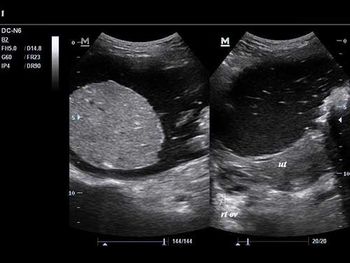

Challenge your diagnostic skills with these images from a young woman with right pelvic pain and a history of amenorrhea.